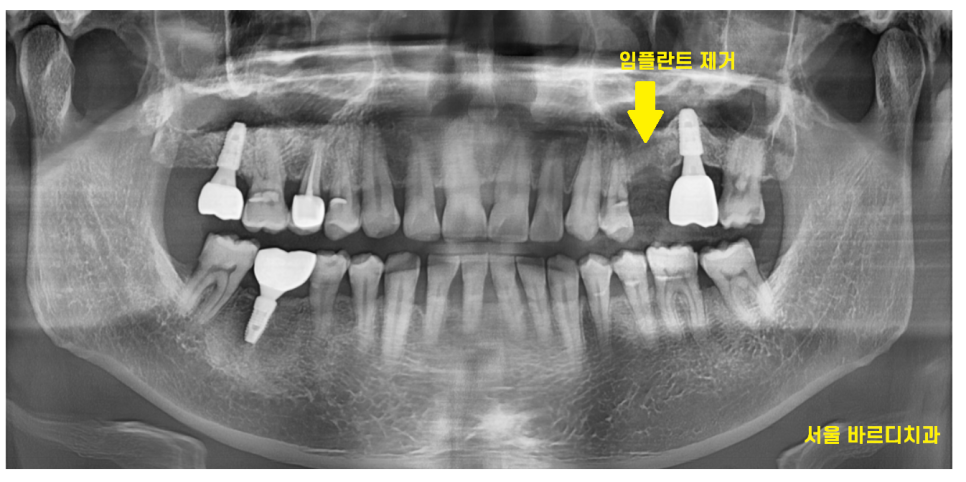

길동 치과에서 임플란트 교체를 하기로

상담해드렸습니다.

23.12.13

찢어진 임플란트를

발치하듯 제거해주고

길동 임플란트 수술을 위하여

뼈이식을 진행해드렸습니다.